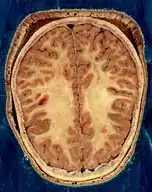

دستگاه عصبی مرکزی شامل مغز و نخاع است که مراکز نظارت بر اعمال بدن هستند. این دستگاه اطلاعات دریافتی از محیط و درون بدن را تفسیر میکند و به آنها پاسخ میدهد. دستگاه عصبی مرکزی از دو بخش مادهٔ خاکستری که بیشتر محتوی جسم سلولی نورونها است و مادهٔ سفید که اجتماع بخشهای میلیندار نورونهاست، تشکیل شده. دستگاه عصبی محیطی شامل تعداد زیادی عصب است که اطلاعات را جمعآوری میکند و به دستگاه عصبی مرکزی میبرد. مغز انسان از حدود ۱۰۰میلیارد (billion) نورون تشکیل شده هست و حدود ۱٫۵کیلوگرم وزن دارد.

مغز شامل: مخ، مخچه و ساقهٔ مغز است. مخ بزرگترین بخش مغز است وتوانایی یادگیری، حافظه، و عملکرد هوشمندانه را دارد. مخچه مهمترین مرکز یادگیری حرکات لازم برای تنظیم حالت بدن و تعادل است. ساقهٔ مغز در قسمت پایینی مغز قرار دارد و شامل مغز میانی، پل مغز و بصلالنخاع است. نخاع درون ستون مهرهها از بصلالنخاع تا کمر امتداد دارد. نخاع مغز را به دستگاه عصبی محیطی وصل میکند. دستگاه عصبی محیطی شامل ۳۱جفت عصب نخاعی و ۱۲جفت عصب مغزی است. دستگاه عصبی محیطی شامل دو بخش پیکری که ارادی است و خودمختار که اعمال غیرارادی ما را بر عهده دارد. دستگاه عصبی خود مختار شامل اعصاب پارا سمپاتیک و سمپاتیک میباشد که اعصاب پارا سمپاتیک باعث برقراری آرامش و اعصاب سمپاتیک در مواقع هیجانی روانی یا جسمی فعال میشوند.